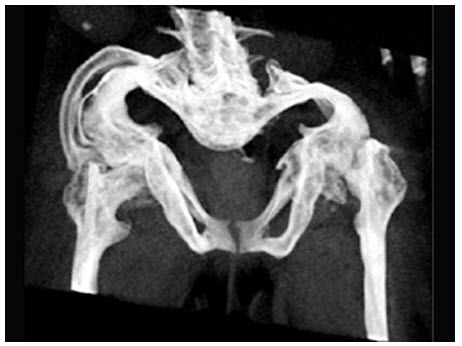

65、多项选择题

女,6个月,CT扫描如图所示,下列说法正确的是()

A.双侧肾盂积水

B.双侧肾门朝向前内方

C.双肾下极融合

D.考虑为异位肾

E.考虑为马蹄肾